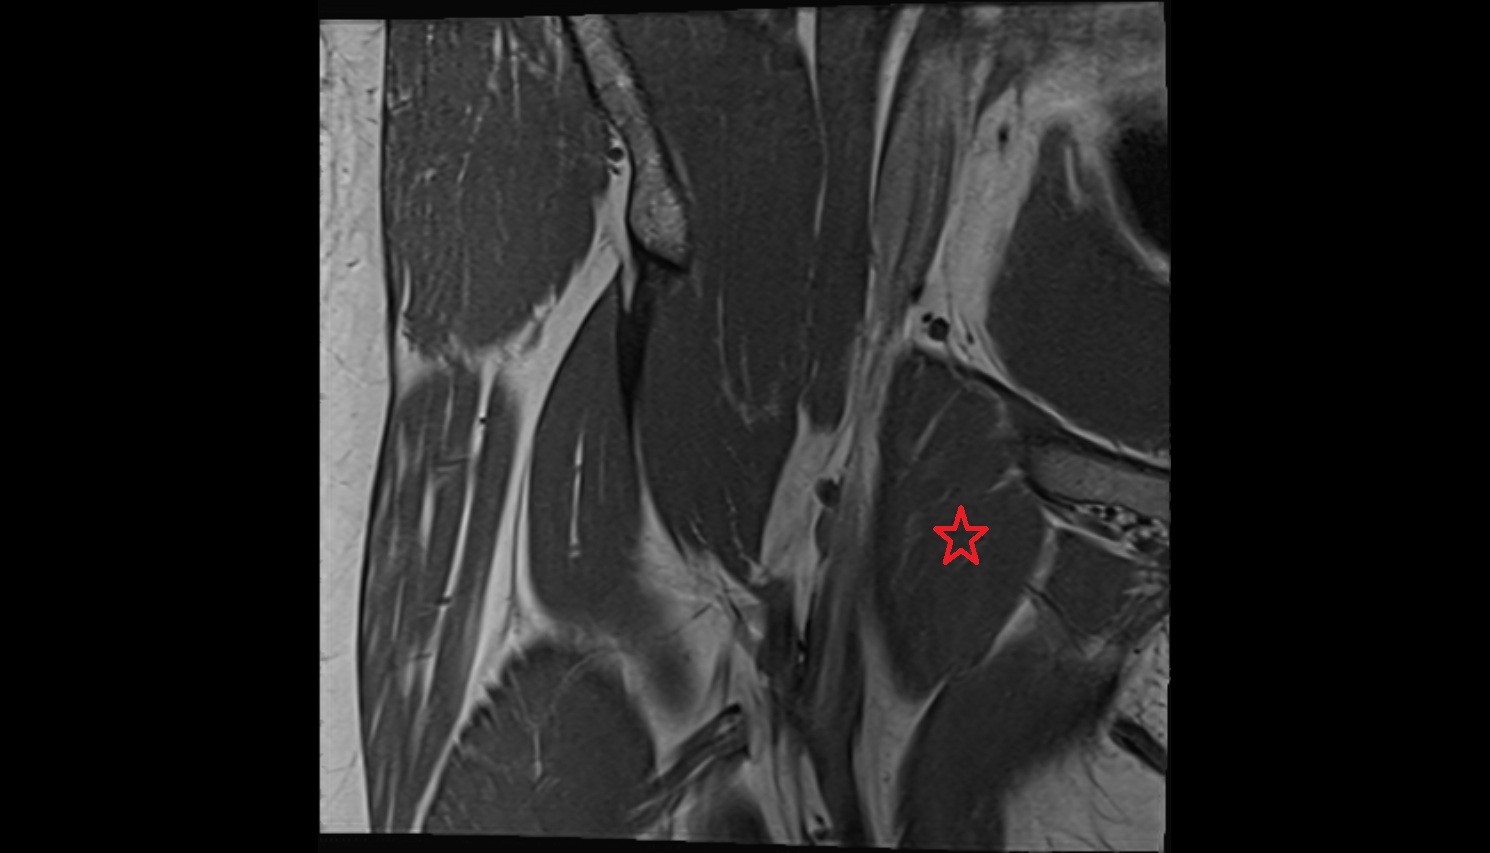

- Biceps femoris muscle (Short head)

- Biceps femoris muscle (Long head)

- Semitendinosus muscle

- Semimembranosus muscle

- Conjoint tendon of biceps femoris & semitendinosus

- Semimembranosus tendon (proximal)